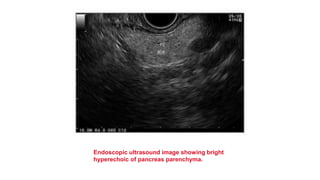

Endoscopic ultrasound image showing bright

hyperechoic of pancreas parenchyma.

Endoscopic ultrasound imageshowing bright hyperechoic of pancreas parenchyma.